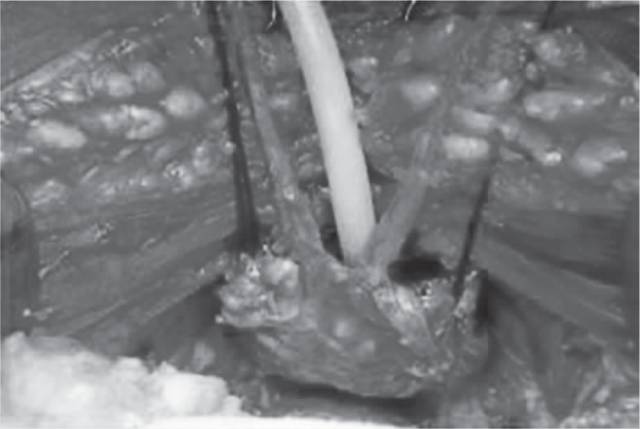

1983年Walsh首次提出前列腺癌(PC)的外科治疗,包括根治性前列腺切除术(RP),该手术涉及在尿道和膀胱之间的整个前列腺腺体切除、双侧精囊切除以及周围组织的充分切除以达到切缘呈阴性(图1和图2)。同时行双侧盆腔淋巴结清扫术。不论任何途径(耻骨后开放,经会阴、腹腔镜、机器人辅助)的RP目标都是达到病灶根治,同时保护尿控和可能的勃起功能。自从Walsh首次介绍了保留神经的解剖性耻骨后途径前列腺根治性切除手术以来,这种方法便成为局灶性PC手术的金标准,并且应用广泛。

图1 开放式耻骨后前列腺根治切除术:前列腺尖部切开